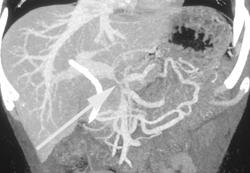

Pancreatic Cancer With Liver Metastases